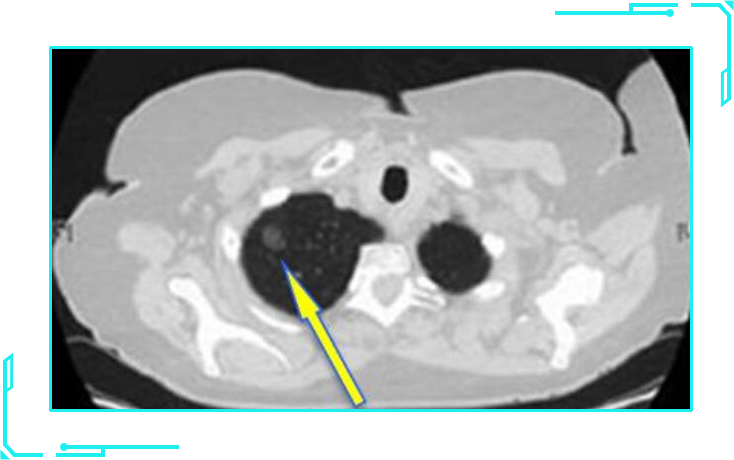

纯实性结节

纯实性结节类似于单独分离的蛋黄,是一个实性且密度较高的病灶。